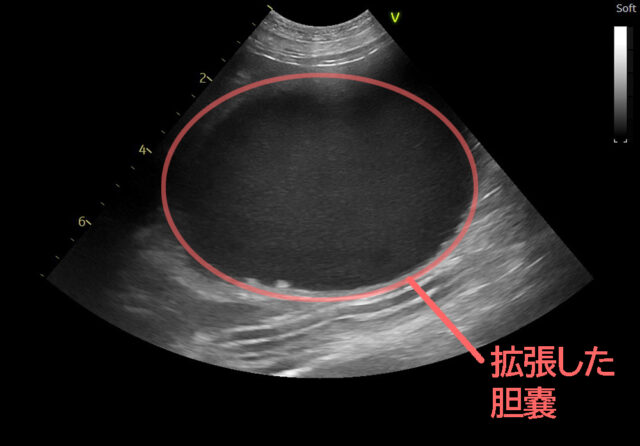

さらに超音波検査を行うと、下の画像のように、胆嚢は拡張し、内部の胆汁は濃く見える像が確認されました。